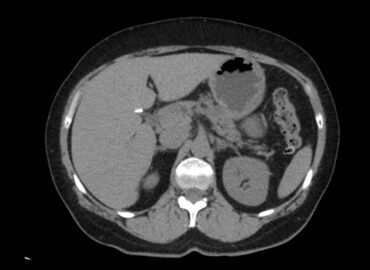

Paciente masculino de 56 años con APP de DM2, que es derivado a nuestro servicio con diagnóstico de síndrome […]